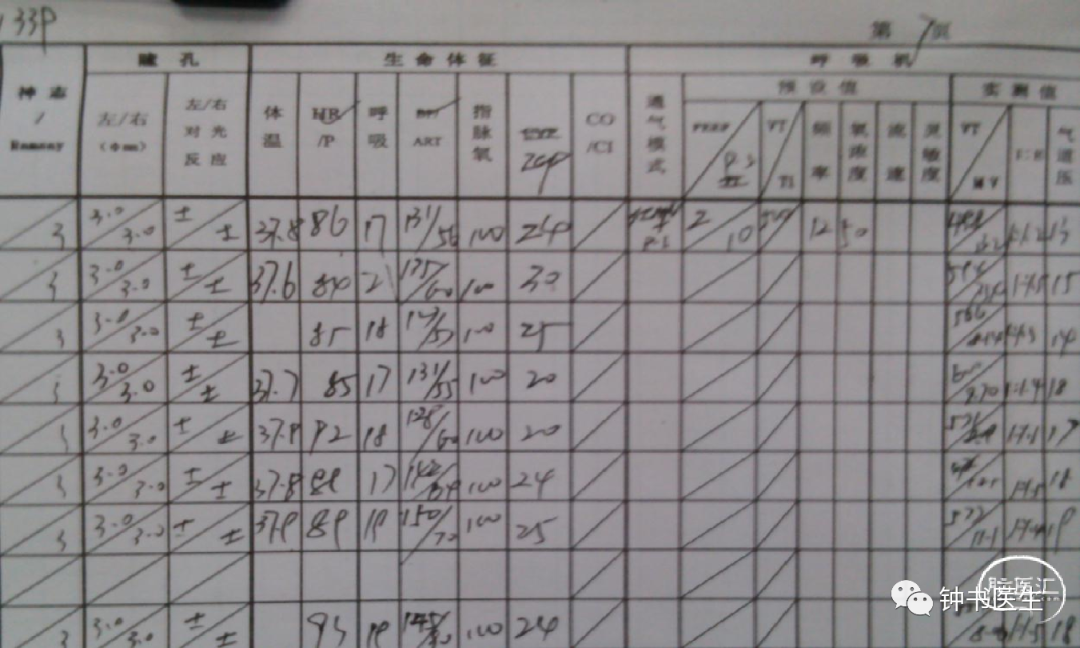

病例1

56y,意识不清伴右侧肢体无力5小时,GCS8分

再灌注损伤(出血):需降压

出血疼痛、烦躁,血压高

镇静镇痛影响神志观察

2012-11-8 CT

左颞部脑梗加重,出血渗出点增多。继续加强镇静镇痛治疗。

2012-11-10 CT

病情趋稳定,转出监护室治疗。